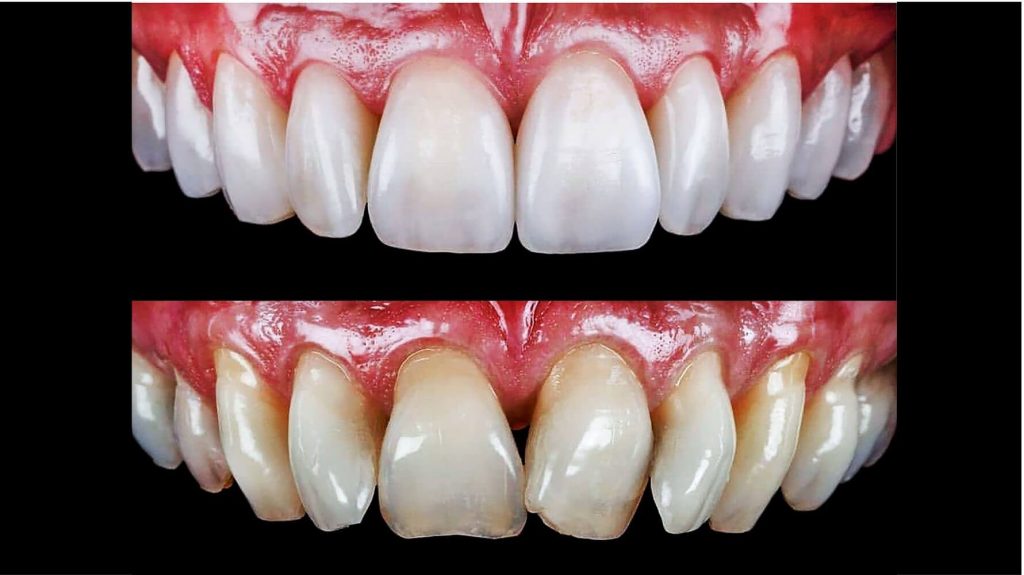

Se você sempre sonhou em ter um sorriso perfeito, estamos aqui para ajudar a tornar esse sonho realidade.

O que são Lentes de Contato Dental?

As lentes de contato dental são finas lâminas cerâmicas, confeccionadas em porcelana de alta resistência, que são aplicadas de forma adesiva sobre a face frontal dos dentes. Este procedimento estético, minimamente invasivo, tem como objetivo promover melhorias funcionais e estéticas, resultando em um sorriso mais harmônico, branco e natural.

Desenvolvidas com tecnologia digital de ponta, as lentes são altamente personalizáveis em forma, cor, tamanho e translucidez, garantindo resultados precisos e naturais para cada paciente.

Diferente das facetas tradicionais, as lentes de contato não exigem desgaste significativo da estrutura dentária em muitos casos, o que proporciona preservação do dente natural, conforto e previsibilidade estética.

Benefícios das Lentes de Contato Dental

Melhoria imediata do sorriso

Correção estética instantânea: manchas, desgastes, pequenos desalinhamentos e diastemas.

Resultados naturais

Sorriso natural e harmônico: personalização

da cor, formato e tamanho dos dentes.

Procedimento minimamente invasivo

Sem dor, sem desgaste excessivo dos dentes.